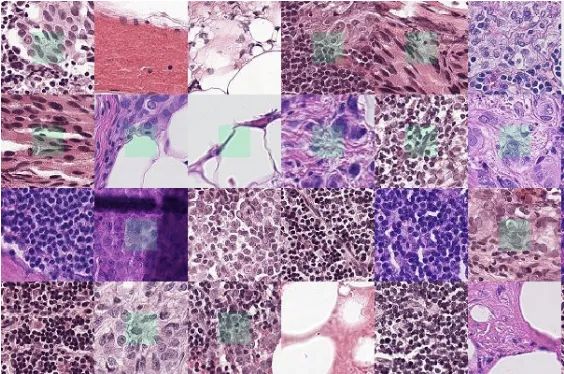

肿瘤数据集

数据集链接:http://m6z.cn/5zCyGj

这一数据集是通过仔细注释几名患有不同器官肿瘤并在多家医院被诊断出的患者的组织图像获得的。该数据集是通过从TCGA存档下载以 40 倍放大倍率捕获的 H&E 染色组织图像创建的。H&E 染色是增强组织切片对比度的常规方案,通常用于肿瘤评估(分级、分期等)。考虑到多个器官和患者的细胞核外观的多样性,以及多家医院采用的丰富染色方案,训练数据集将能够开发出开箱即用的稳健且可推广的细胞核分割技术。